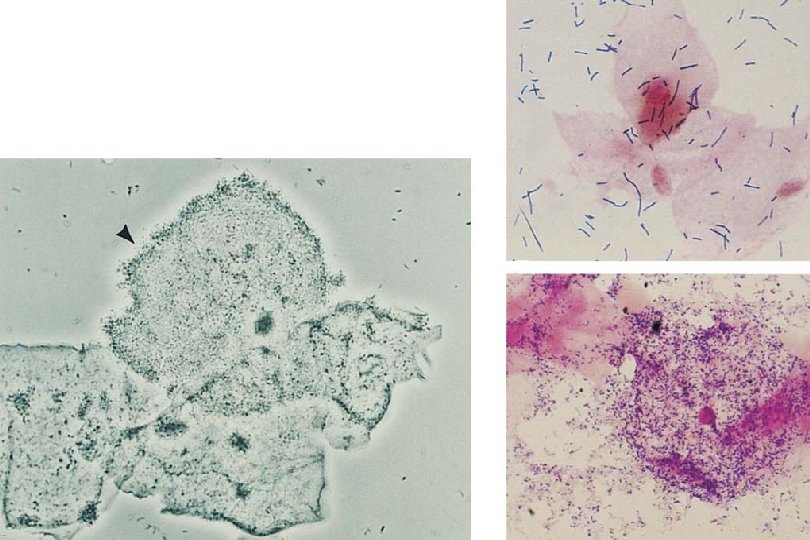

Diagnosis of BV · Clinical findings (Amsel criteria): >3 of the following: - Homogeneous discharge, smoothly coating vaginal walls and - introitus p. H >4. 5 Clue cells (>20%) on saline microscopy Amine odor on addition of KOH (+whiff test) • Putrescine, cadaverine • BV Blue® test: uncertain clinical utility · Gram stain findings (Nugent scale) - Based on number of lactobacilli and other bacterial - morphotypes 0 -9 scale: 0 -3 normal, 4 -6 borderline, 7 -9 definite BV Primarily research, but clinically useful in trained hands

Bacterial Vaginosis Wet Prep: Clue Cell Vaginal Discharge